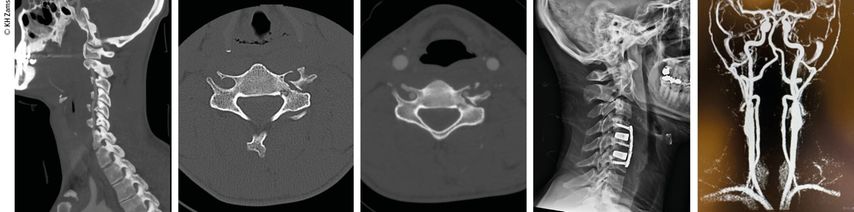

Die Therapieentscheidung erfolgt patientenindividuell und richtet sich neben der Graduierung an der Klinik und den möglichen Begleitverletzungen oder Vorerkrankungen. Therapieziele sind die Vermeidung sekundärer ischämischer Ereignisse, die Reperfusion des betroffenen Gefäßes und die Prävention neurologischer Defizite durch Schaffen stabiler Verhältnisse (Abb.1).

Abb. 1: Therapieziele sind die Vermeidung sekundärer ischämischer Ereignisse, die Reperfusion des betroffenen Gefäßes und die Prävention neurologischer Defizite durch Schaffen stabiler Verhältnisse

Der interdisziplinäre Ansatz ist entscheidend. Liegt beispielsweise eine instabile HWS-Verletzung mit Vertebralis-Dissektion vor, so ist die Wiederherstellung stabiler Verhältnisse für u.a. die A. vertebralis vordergründig (Abb.2–4). Dieser operative Eingriff erfolgt bereits unter therapeutischer Heparinisierung. Je nach Ausmaß der Gefäßverletzung wird dabei ein- oder zweizeitig die endovaskuläre/offene Therapie zur Gefäßreperfusion durchgeführt. Aktuelle interdisziplinäre Therapieempfehlungen:

Abb. 2: Fallbeispiel: Mann, 57a, Z.n. Fahrradsturz, stabile Fraktur des Proc. artic. C2 r. mit Dissektion der A. vertebralis r. mit asymptomatischem Substanzdefekt im hinteren Stromgebiet (cMRT), Heparintherapie initial, anschließend APT

Abb. 3: Mann, 30a, Z.n. Snowboardsturz, Rotations-/Subluxationsverletzung C5/6 mit Dissektion der A. vertebralis r.; Zervikobrachialgie mit sensiblem Defizit; OP unter Heparintherapie, APT für 3 Monate

Abb. 4: Mann, 28a, Z.n. Schisturz; instabile Teardrop-Verletzung mit Dissektion A. vertebralis l.; Zervikobrachialgie mit Dysästhesie C6, mehrere kleine embolische Infarkte vertebrobasilär mit Koordinationsstörung; OP + Heparintherapie initial, anschließend APT